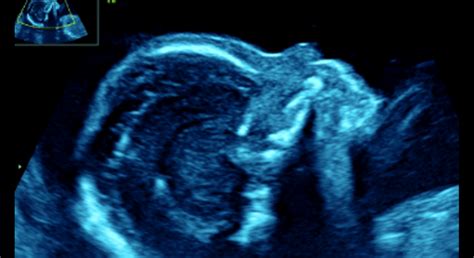

V druhom trimestri dieťa rýchlo rastie a jeho orgány sa ďalej vyvíjajú a zdokonaľujú. V tomto období sa začína aktívne hýbať, čo matka prvýkrát cíti ako jemné kopanie či pohyby. Dieťa je teraz veľké ako broskyňa alebo citrón a jeho váha sa pohybuje od 20 do 25 gramov v raných týždňoch tohto trimestra, postupne narastajúc až k 600 gramom v jeho závere (okolo 24. týždňa).

Čuchové poháriky sa vyvíjajú a dieťa začína vnímať zvuky z okolia, vrátane tlkotu srdca matky. Očné viečka sú už vytvorené a zakrývajú oči, ktoré sa otvoria neskôr. Vytvára sa bránica, ktorá oddeľuje srdce a pľúca od tráviacich orgánov. V tomto období je už možné dieťa merať dvoma spôsobmi: od temena hlavy ku kostrči a od temena hlavy k pätičkám.

Niektoré ženy pociťujú zvýšené libido, zatiaľ čo iné ho stratia kvôli nevoľnostiam. Pohyby dieťaťa, ktoré matka začína cítiť, sú jedným z najkrajších zážitkov tohto obdobia. V tomto trimestri sa zvyčajne vykonáva podrobný ultrazvuk, ktorý umožňuje dôkladne skontrolovať vývoj plodu a jeho orgánov.